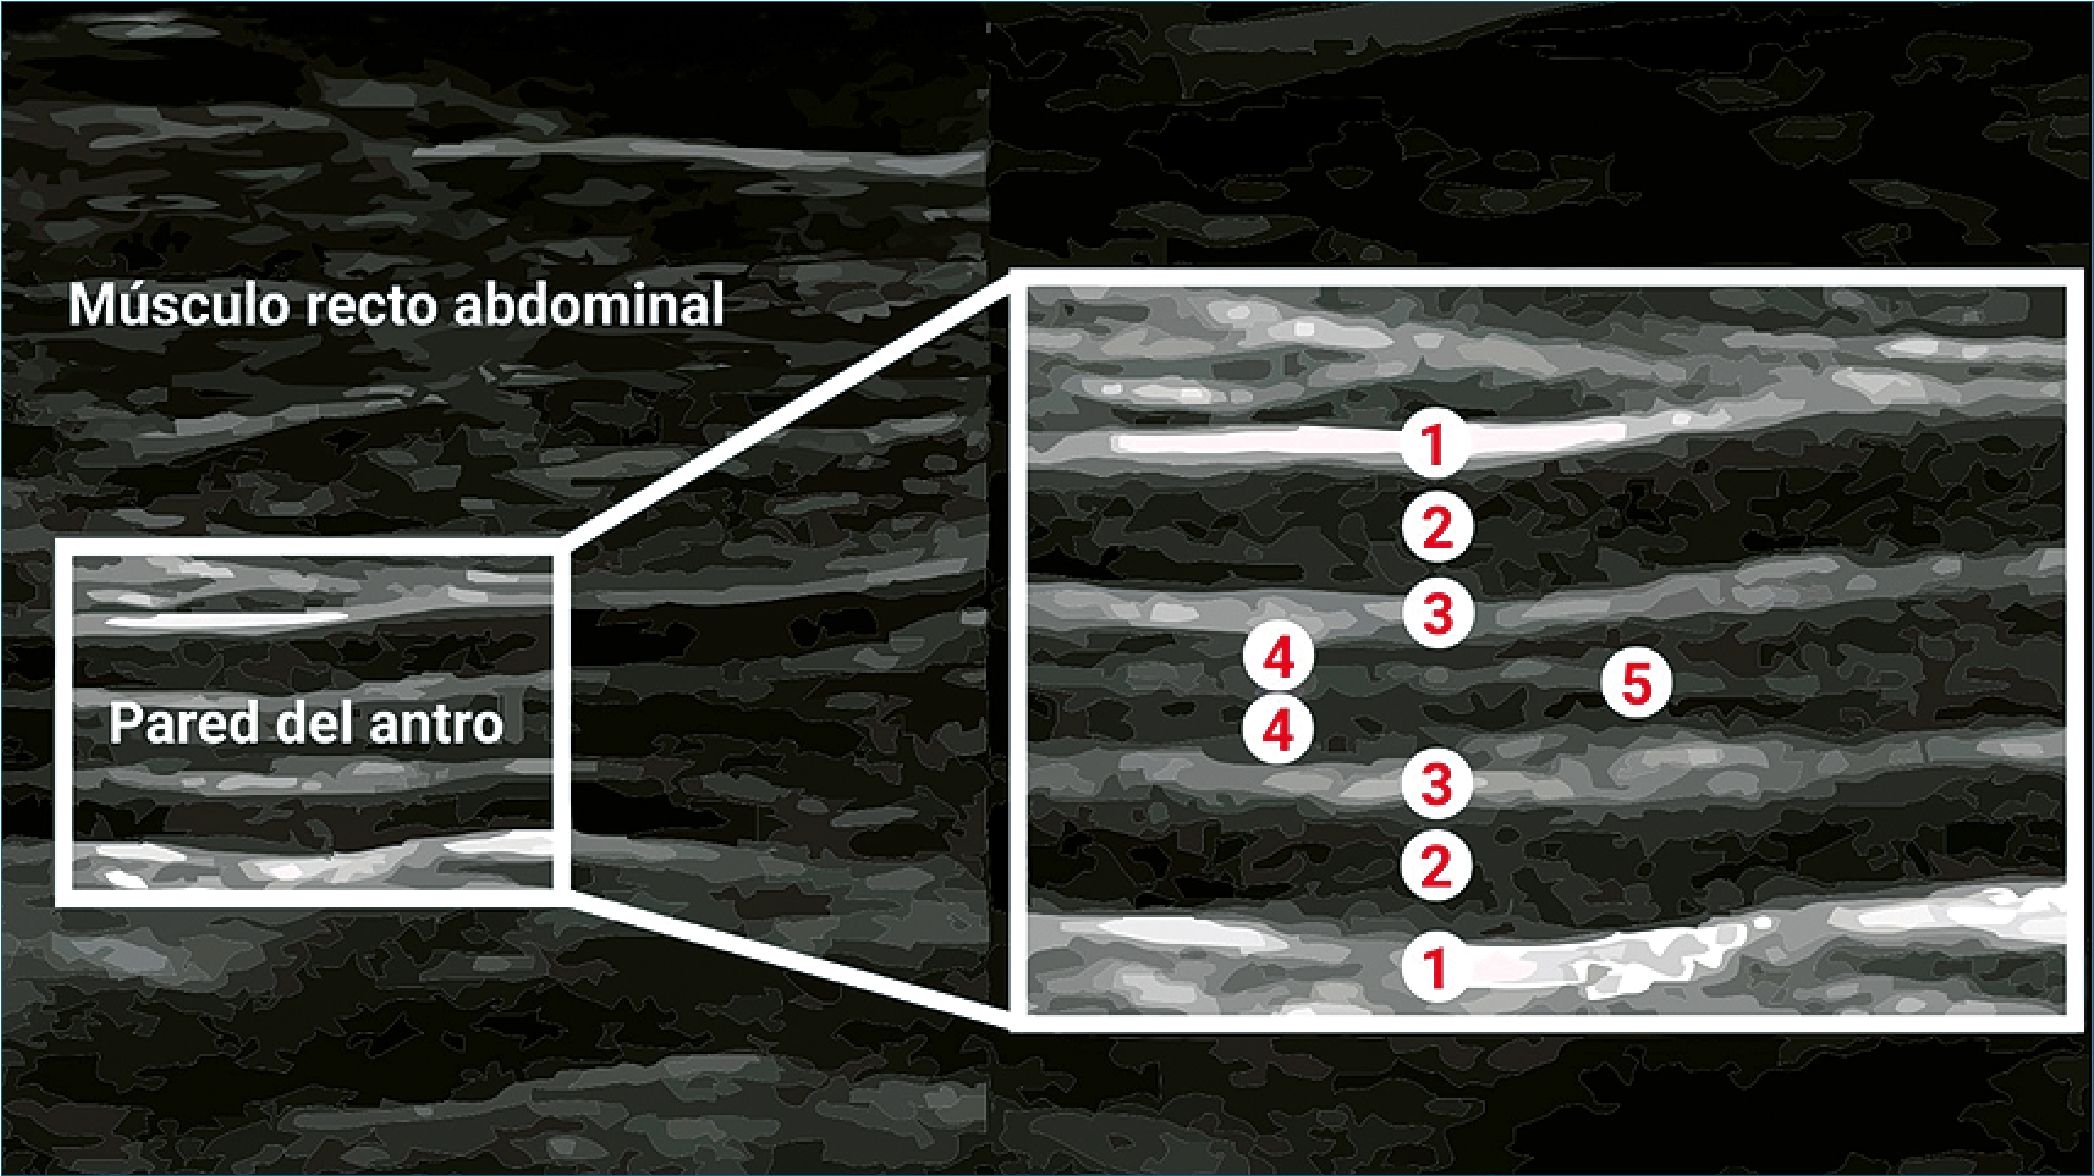

La capa muscular del antro gástrico consta de cinco capas, que desde el interior hacia el exterior, se detallan en la Figura 3 y la Tabla 3[16].

Figura 1. Anatomía del estómago, destacando el antro gástrico y sus capas. Tomado y traducido de 10.1016/j.bjae.2019.03.003[13].

Tabla 3. Capas del antro gástrico

| Capas del antro gástrico |

| 1. Serosa |

| 2. Muscularis propiae |

| 3. Submucosa |

| 4. Muscularis mucosa |

| 5. Interface mucosa-aire |

Figura 3. Capas del antro gástrico por ultrasonido.